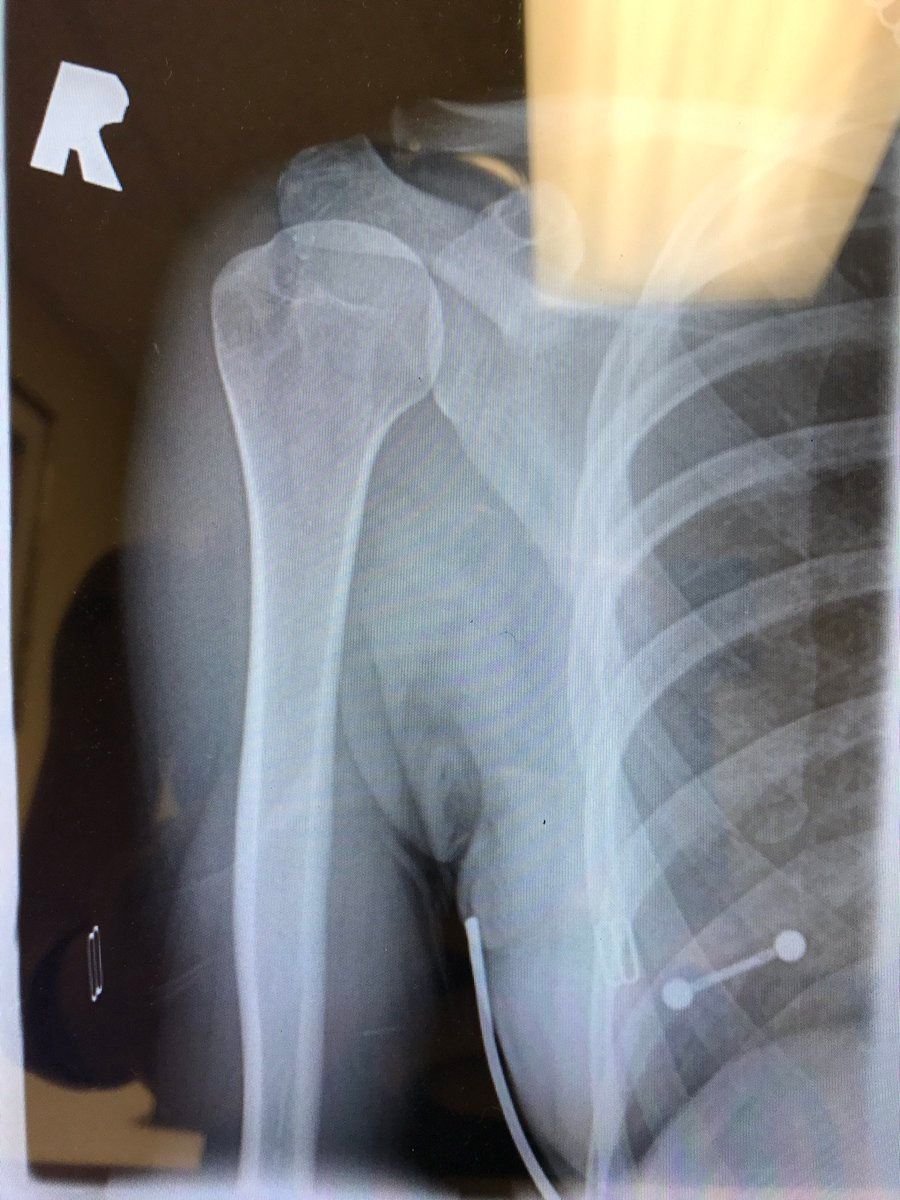

@brassiest I once did that with an x-ray of my shoulder and it was the afternoon before I realized this piercing oops